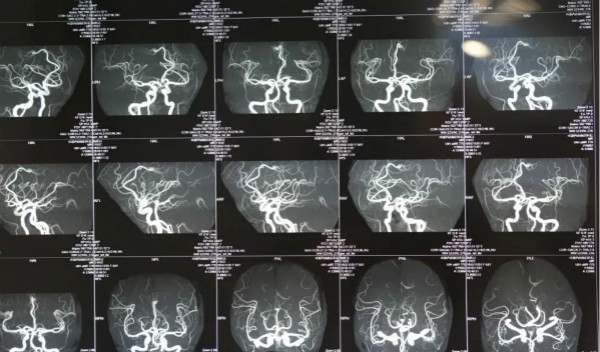

腦動(dòng)脈瘤不是常規(guī)意義上的腫瘤,而是腦血管某一段局限囊性膨出,類(lèi)似于汽車(chē)輪胎側(cè)壁鼓包,動(dòng)脈瘤一旦破裂可以導(dǎo)致致死性出血,是很兇險(xiǎn)的出血性血管病,那么腦動(dòng)脈瘤破裂能活多久呢?

臨床上,腦動(dòng)脈瘤根據(jù)病情可以分為一級(jí)、二級(jí)和三級(jí)。目前,腦動(dòng)脈瘤可以通過(guò)開(kāi)顱夾閉來(lái)進(jìn)行治療。另外,還可以做介入治療,也就是把動(dòng)脈瘤做栓塞治療。所以一般來(lái)說(shuō),患者的預(yù)后主要取決于患者術(shù)前的狀態(tài),腦動(dòng)脈瘤破裂能活多久,一定要具體情況具體分析。